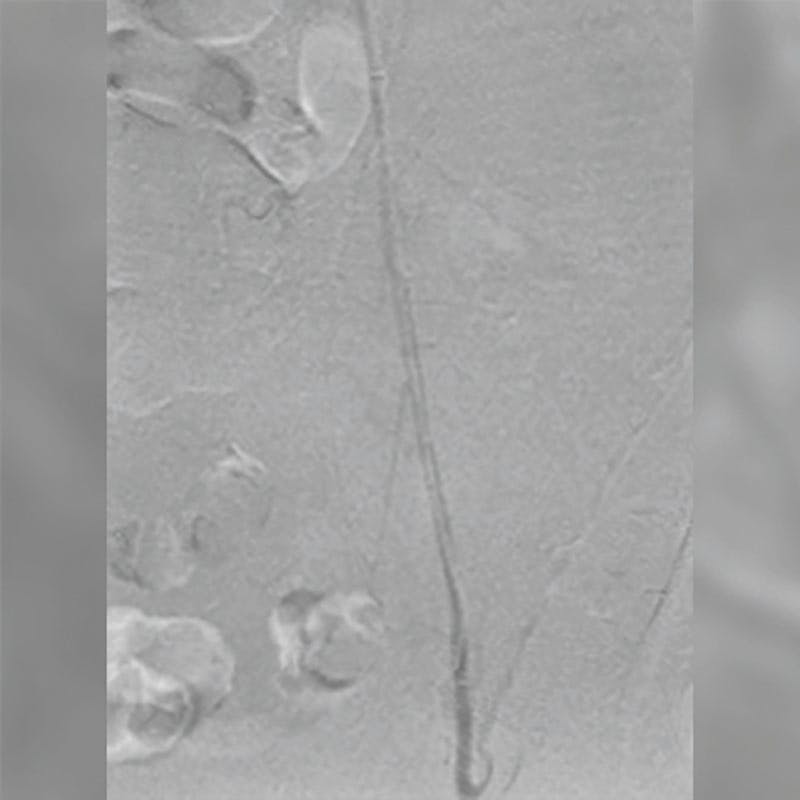

After informed consent, we elected to obtain a venogram with intravascular ultrasound (IVUS) and pullback pressures, as the CT scan workup showed a nutcracker phenomenon. Standard access of the right femoral vein was performed under ultrasound guidance. The left renal vein was cannulated and IVUS was used along with pullback pressures, which did not suggest that there was significant compression of the renal vein by the superior mesenteric artery. A venogram was obtained and showed significant reflux in the ovarian vein via collaterals (Figure 1).

Figure 1. Pre-embolization venography demonstrating recurrent reflux in the left ovarian vein with collateral filling following prior low pelvic coil placement.